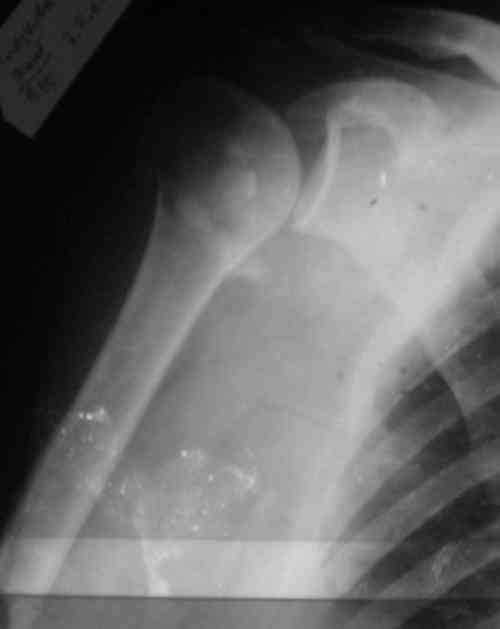

Снимки на 1-е сутки после репозиции и на 8- сутки после репозиции.

Пожалуйста

Головка плечав небольшом варусе или это проекционное?

На 20-е сутки снял гипс, одел фиксирующюю

ортопедическую повязку. Вот контроль. Как видно, стояние хорошее, уже формируется костный мозоль.

Думаю еще недели 3 продолжать фиксацию.

-Головка плеча в небольшом варусе или это

проекционное?

Да, там имеем небольшой варус, надеемся, что в будущем проблемы не будет.